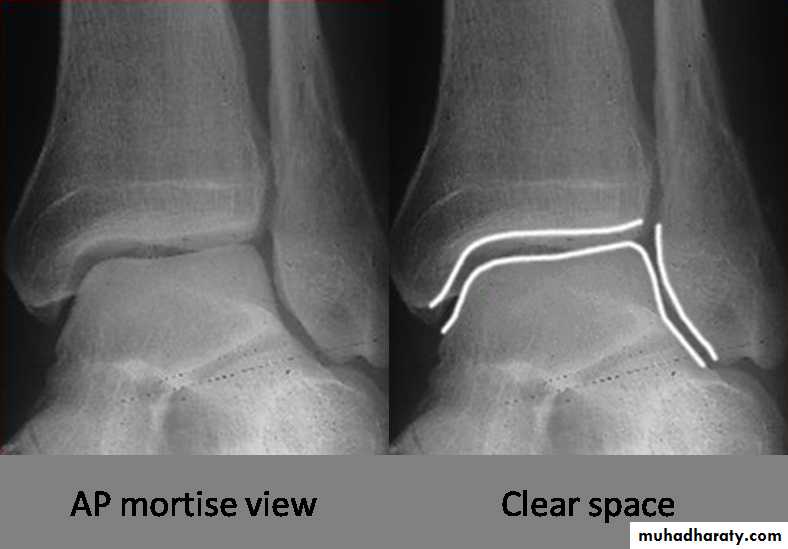

X ray: it is essential to do anteroposterior, lateral and mortise views (The AP mortise view is done with the leg internally rotated 15-20o ,This view permits examination of the articular space (clear space). The width of the clear space between the talus and the articular surfaces of the medial malleolus, the tibial plafond and the lateral malleolus should be equal.

X- ray shows the type of fractures, Any shift, tilt or displacement in talus is serious, If the fibular fractures above the tibiofibular joint there must be a diastasis.